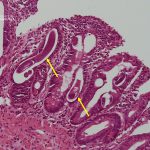

- Presença de larvas de Strongyloides stercoralis em biópsia duodenal (setas).